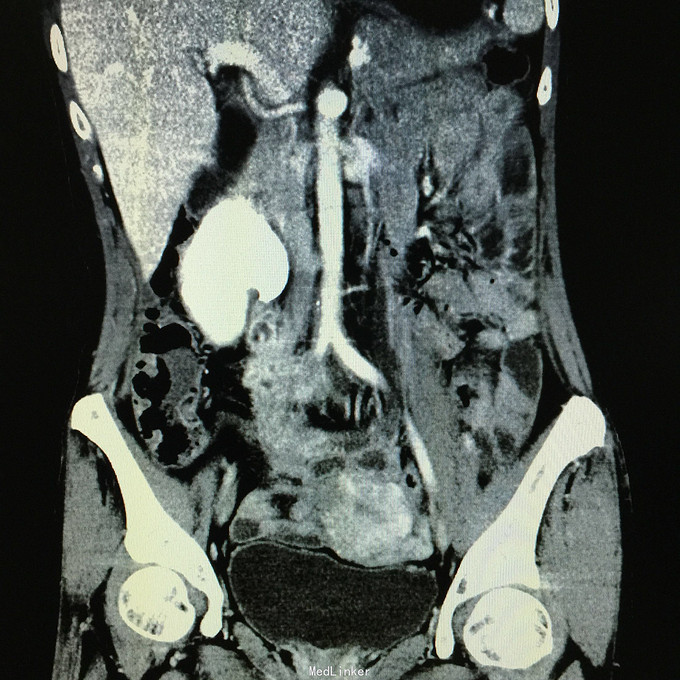

查体无特殊。 辅助检查:中下腹CT平扫+增强+CTU+CTA示:1.右输尿管中上段病变,考虑恶性病变,周围多发淋巴结转移,髂总动脉及髂外动脉起始部、髂内动脉中上段受侵闭塞,右侧腰大肌可疑受侵;建议输尿管镜检查;右肾重度积水,右肾功能明显受损。2.CTA示:右肾动脉纤细,肝右动脉起源于肠系膜上动脉。3.子宫体密度不均匀,建议MRI检查。中下腹MRI平扫+增强+MRU检查结果类似。

患者术后2月出现反复臀部疼痛,左侧为主,疼痛跑迷宫为隐痛,于翻身及活动时加重,卧床休息可稍缓解,多于下午出现,伴有发热,最高达39℃,在当地医院予“氟康唑”及止痛治疗后稍有缓解,但仍反复发热。后疼痛加剧,并出现双下肢疼痛,以大腿外侧为主,无间歇性跛行,无小腿及双足麻木疼痛不适,行对症治疗后效果不佳,于2015-10-9再次返院,予消炎止痛、营养支持及营养神经等治疗。查CT及MRI均提示骶髂关节炎症及腹膜后巨大病变,右侧髂总动脉及髂内、外动脉上段、右侧腰大肌受累。2015-10-15 14:00患者出现右下肢剧烈疼痛、右下肢乏力和麻木,随后出现2次血便,每次量约100ml,暗红色,无腹胀、腹痛等不适,查血提示白细胞 28.17*10E9/L,中性粒绝对值 25.33*10E9/L,血红蛋白56g/L,予止血、输血、抗真菌、止痛等治疗。19:00再次出现右下肢剧烈疼痛伴右下腹痛,查体:BP 80-90/50-60mmHg,P 100-106次/分,R 23次/分,SpO2 100%。右下腹轻压痛,反跳痛阴性,右下肢蹲背伸及踝背伸肌力II-III级,立即行全腹CT检查,示右髂总动脉假性动脉瘤破裂,予加强输注浓缩红细胞及补液支持治疗。清介入科会诊,考虑脓肿和感染为介入血管腔内支架置入治疗的禁忌症,建议予血管外科行开放手术,予患者及家属沟通,并转外院血管外科进一步治疗。